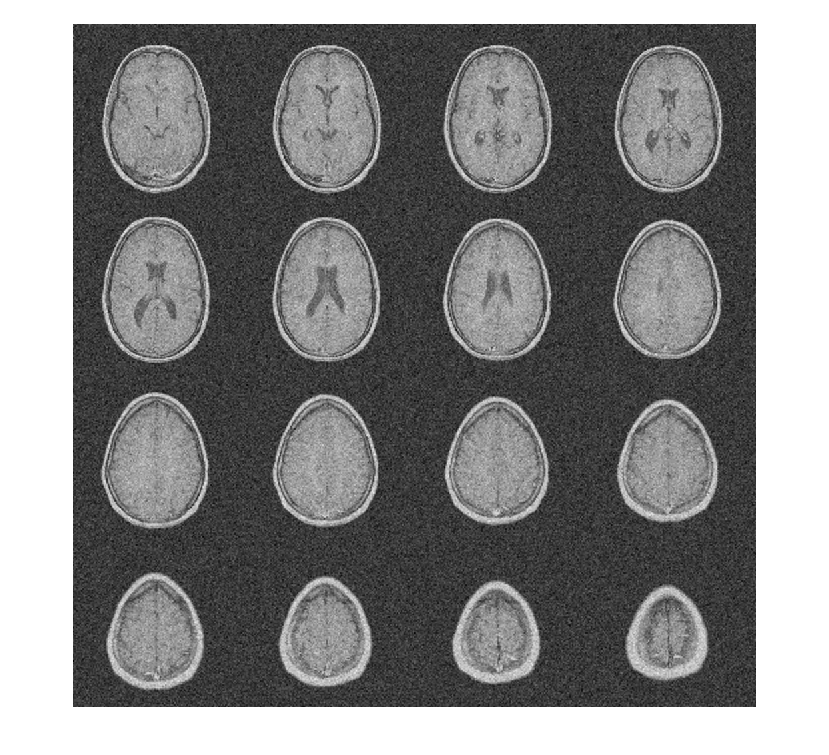

Чтобы продемонстрировать это, рассмотрите набор данных MRI, состоящий из 16 срезов. Гауссов шум со стандартным отклонением 10 был добавлен к исходному набору данных. Отобразите шумный набор данных.

load MRI3D; montage(reshape(noisyMRI,[128 128 1 16]),'DisplayRange',[]);

Обратите внимание на то, что исходный ОСШ до шумоподавления составляет приблизительно 11 дБ.

Denoise набор данных MRI вниз к уровню 4 с помощью и DT-CWT и DWT. Подобные длины фильтра вейвлета используются в обоих случаях. Постройте получившийся ОСШ как функцию порога. Отобразите результаты denoised и для DT-CWT и для DWT, полученного в лучшем ОСШ.

[imrecDTCWT,imrecDWT] = helperCompare3DDenoising(origMRI,noisyMRI); figure; montage(reshape(imrecDTCWT,[128 128 1 16]),'DisplayRange',[]); title('DT-CWT Denoised Volume'); figure; montage(reshape(imrecDWT,[128 128 1 16]),'DisplayRange',[]); title('DWT Denoised Volume');